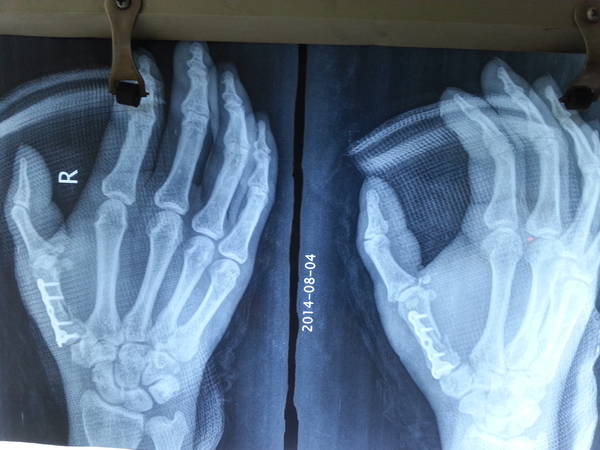

[断指再植] 几例拇指离断

20140804_094134.jpg